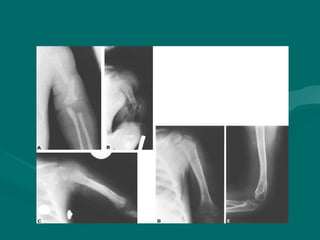

DDIIAAGGNNOOSSTTIICCOO PPOORR IIMMAAGGEENN

• PPrrooyyeecccciióónn

aanntteerrooppoosstteerriioorr yy llaatteerraall

• EEss ppoossiibbllee ddeetteeccttaarr

ffrraaccttuurraass ppaattoollóóggiiccaass::

– EExxiisstteenncciiaa ddee llaa ppaarrss

ccoonnddiilliiaannaa..

– QQuuiissttee óósseeoo..

– DDiissppllaassiiaa ffiibbrroossaa..

– GGrraannuulloommaa eeoossiinnooffíílliiccoo..

– LLeessiioonneess mmeettaassttáássiiccaass eenn

hhúúmmeerroo..